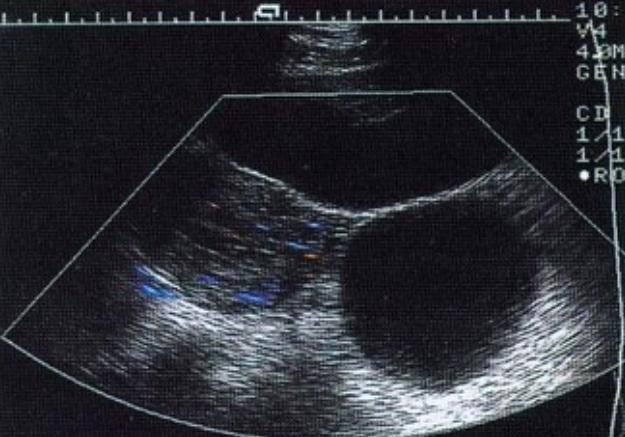

2016年辽宁一59岁女子去医院取避孕环,几年后,她用手机播放歌曲时,发现医生悄悄在她子宫里安了监听器,导致她肚子很难受,女子一气之下,把医院告上法庭……   今年9月,辽宁葫芦岛有个官司判下来了,听完这事儿的来龙去脉,我总觉得跟听了段离奇小说似的。主角是59岁的叶大姐,她这辈子可能都没想过,自己会因为六年前的一次手术,跟医院打上两场官司。   事儿得从2016年说起,那年叶大姐去当地一家医院取避孕环,本来是个挺常规的小手术,术后恢复也没出啥大问题。   可谁能想到,过了好几年,叶大姐慢慢觉得不对劲了——她发现自己一用手机放歌,肚子就不得劲,总感觉里面有东西跟着“晃”,像是在“共鸣”。   一开始她还没太往心里去,可这种不舒服的感觉越来越频繁,她心里的疑团也越来越大,最后竟琢磨出一个让人大跌眼镜的结论:当年给她做手术的医生,肯定是趁她不注意,在她子宫里装了个“监听器”!   这个想法一旦冒出来,就跟扎了根似的。叶大姐越想越觉得是这么回事,今年1月,她特意去做了个彩超,拿到报告后,指着上面“左附件区小囊肿”“囊性回声”这几个字,更笃定了——这不就是那个高科技监听器嘛!   为了讨个说法,她直接把当年的医院和那位高姓医生告上了法庭,诉求也挺明确:让医院免费把“监听器”取出来,再赔偿她的损失。   可打官司不是靠“觉得”就行的,得讲证据。从绥中县人民法院到葫芦岛市中级人民法院,两场官司下来,结果都是叶大姐败诉。   法官的理由其实挺简单:你说有监听器,那东西在哪儿呢?所有的检查报告翻遍了,连一点金属异物的影子都没有,总不能凭感觉就认定医院做了这种事吧?   法律上有个规矩叫“谁主张,谁举证”,叶大姐拿不出能证明监听器存在的实锤证据,败诉自然是难免的。   她把医学报告里的“囊性回声”当成“监听器”的证据,在法律上根本站不住脚,毕竟法院认的是实打实的检查结果,不是个人对着专业术语的“脑补”。   其实抛开官司不说,单说叶大姐想象中的“子宫监听器”,在技术上也基本不可能实现。先不说这么个小东西要在人体里常年工作,能源从哪儿来——总不能靠人体自身供电吧?   再就是信号传输的问题,人体里大部分是水和组织,对无线电信号的屏蔽效果特别好,想从盆腔深处把声音传出去,简直跟天方夜谭似的。   更别提人体内部本身就“吵”得很,心跳声、肠子蠕动的声音,早就把所谓的“监听声音”盖得严严实实,就算真有监听器,也啥都听不见。   叶大姐会有这样的想法,说到底还是因为不懂“囊性回声”这些医学术语,只能用自己能理解的方式去填补认知空白,结果越想越偏,把正常的身体反应和医学现象,跟“被监听”联系到了一起。   那报告里的“囊性回声”到底是啥?其实在医学上再普通不过了。做超声波检查时,这个词就是形容某个部位充满了液体,像个小水泡一样。   叶大姐报告里那个2.7×2.4厘米的小囊肿,再加上一点盆腔积液,对于一个快60岁、还做过子宫次全切手术的女性来说,是很常见的情况,而且多数都是良性的,根本不用这么恐慌,跟高科技监听器更是八竿子打不着。   这场官司说到底,就是一场因为信息不对等引发的闹剧。叶大姐可能是因为身体不舒服,又不懂医学知识,才会产生这样的误解,可维权得靠事实和专业鉴定,不是靠想象力。   最后不仅自己折腾半天没结果,还浪费了不少公共资源。医患之间本来就需要信任,一旦因为认知偏差产生猜疑,很容易把小事闹大。